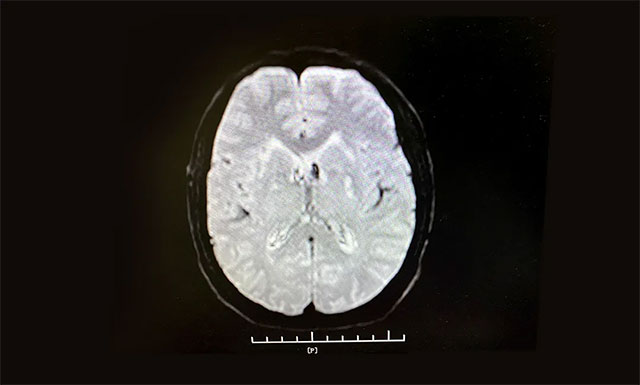

從急診科11:11接診,11:13建立靜脈通道,到11:28影像科CT平掃排除腦出血,并告知家屬,經(jīng)反復(fù)溝通到11:56接受溶栓,門診、急診科、腦血管病科、影像科、檢驗(yàn)科等多個(gè)科室通力合作,發(fā)揮多學(xué)科聯(lián)動(dòng)優(yōu)勢(shì),無(wú)縫對(duì)接,DNT (Door to Needle Time——從患者入院急癥科到接受溶栓治療時(shí)間)用時(shí)為45分鐘,為搶救患者的大腦功能贏得了寶貴時(shí)間。

▲ 根據(jù)急診CT影像結(jié)果,排除患者腦出血